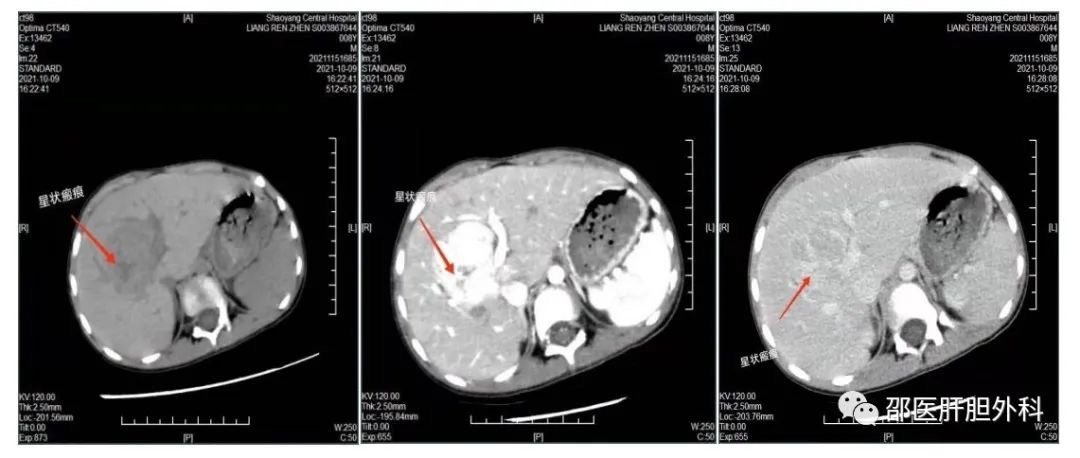

该患儿7岁10个月,因外伤意外发现肝占位,体积(6厘米*5厘米),完善腹部增强CT及MRI,考虑局灶性结节增生,但不排除恶性肿瘤可能。为求手术治疗入住该院小儿外科,入科后进一步完善肝功能储备(ICG<10%),三维重建,并邀请影像科、肝胆外科、小儿外科、麻醉科开展了MDT讨论。考虑到患儿肝肿瘤位于肝中叶(IV+VIII段),周围广泛的肝静脉及门静脉血管包绕肝肿瘤,术中极容易发生大出血,术前请示副院长郑核共同阅片,并结合三维重建图,一起充分预估了手术风险和困难,规划好手术方案。术前反复告知患者家属手术难度大,手术风险高,家属知情理解病情后仍坚持手术治疗,最终决定行腹腔镜肝肿瘤切除术。

在一番充分准备后,10月27日,在副院长郑核和科室主任禹旭平的指导下,由唐立华主任医师和袁中生副主任医师主刀共同完成了腹腔镜肝肿瘤切除。专家们术中采用了间断阻断肝门控制出血,精细解剖第一肝门和第二肝门,充分显露肝脏的管道系统,先结扎后离断,确切止血,避免了撕破肝静脉、门静脉造成出血和术后胆瘘发生。尽管手术难度大,大出血风险高,但凭借专家扎实的肝脏解剖学知识和熟练的肝肿瘤切除操作技术,手术顺利完成,术中出血量少,约50毫升。